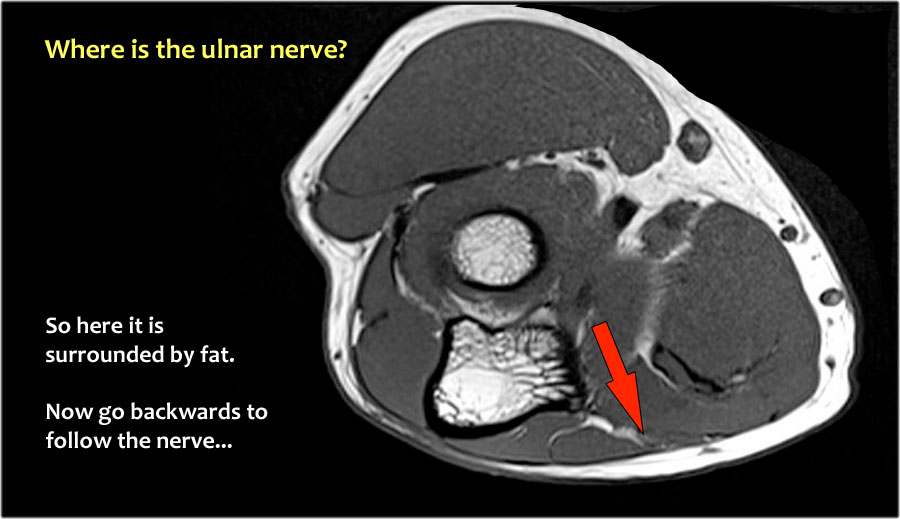

Một cách để thực hiện là đi theo các cấu trúc về phía xa cho đến khi tìm thấy dây thần kinh trụ ở phía xa tại vị trí bình thường của nó ở vùng cẳng tay gần được bao quanh bởi mô mỡ.

Sau đó khi bạn theo dõi nó về phía gần, bạn sẽ nhận thấy rằng đây là một trường hợp chuyển vị dưới da.